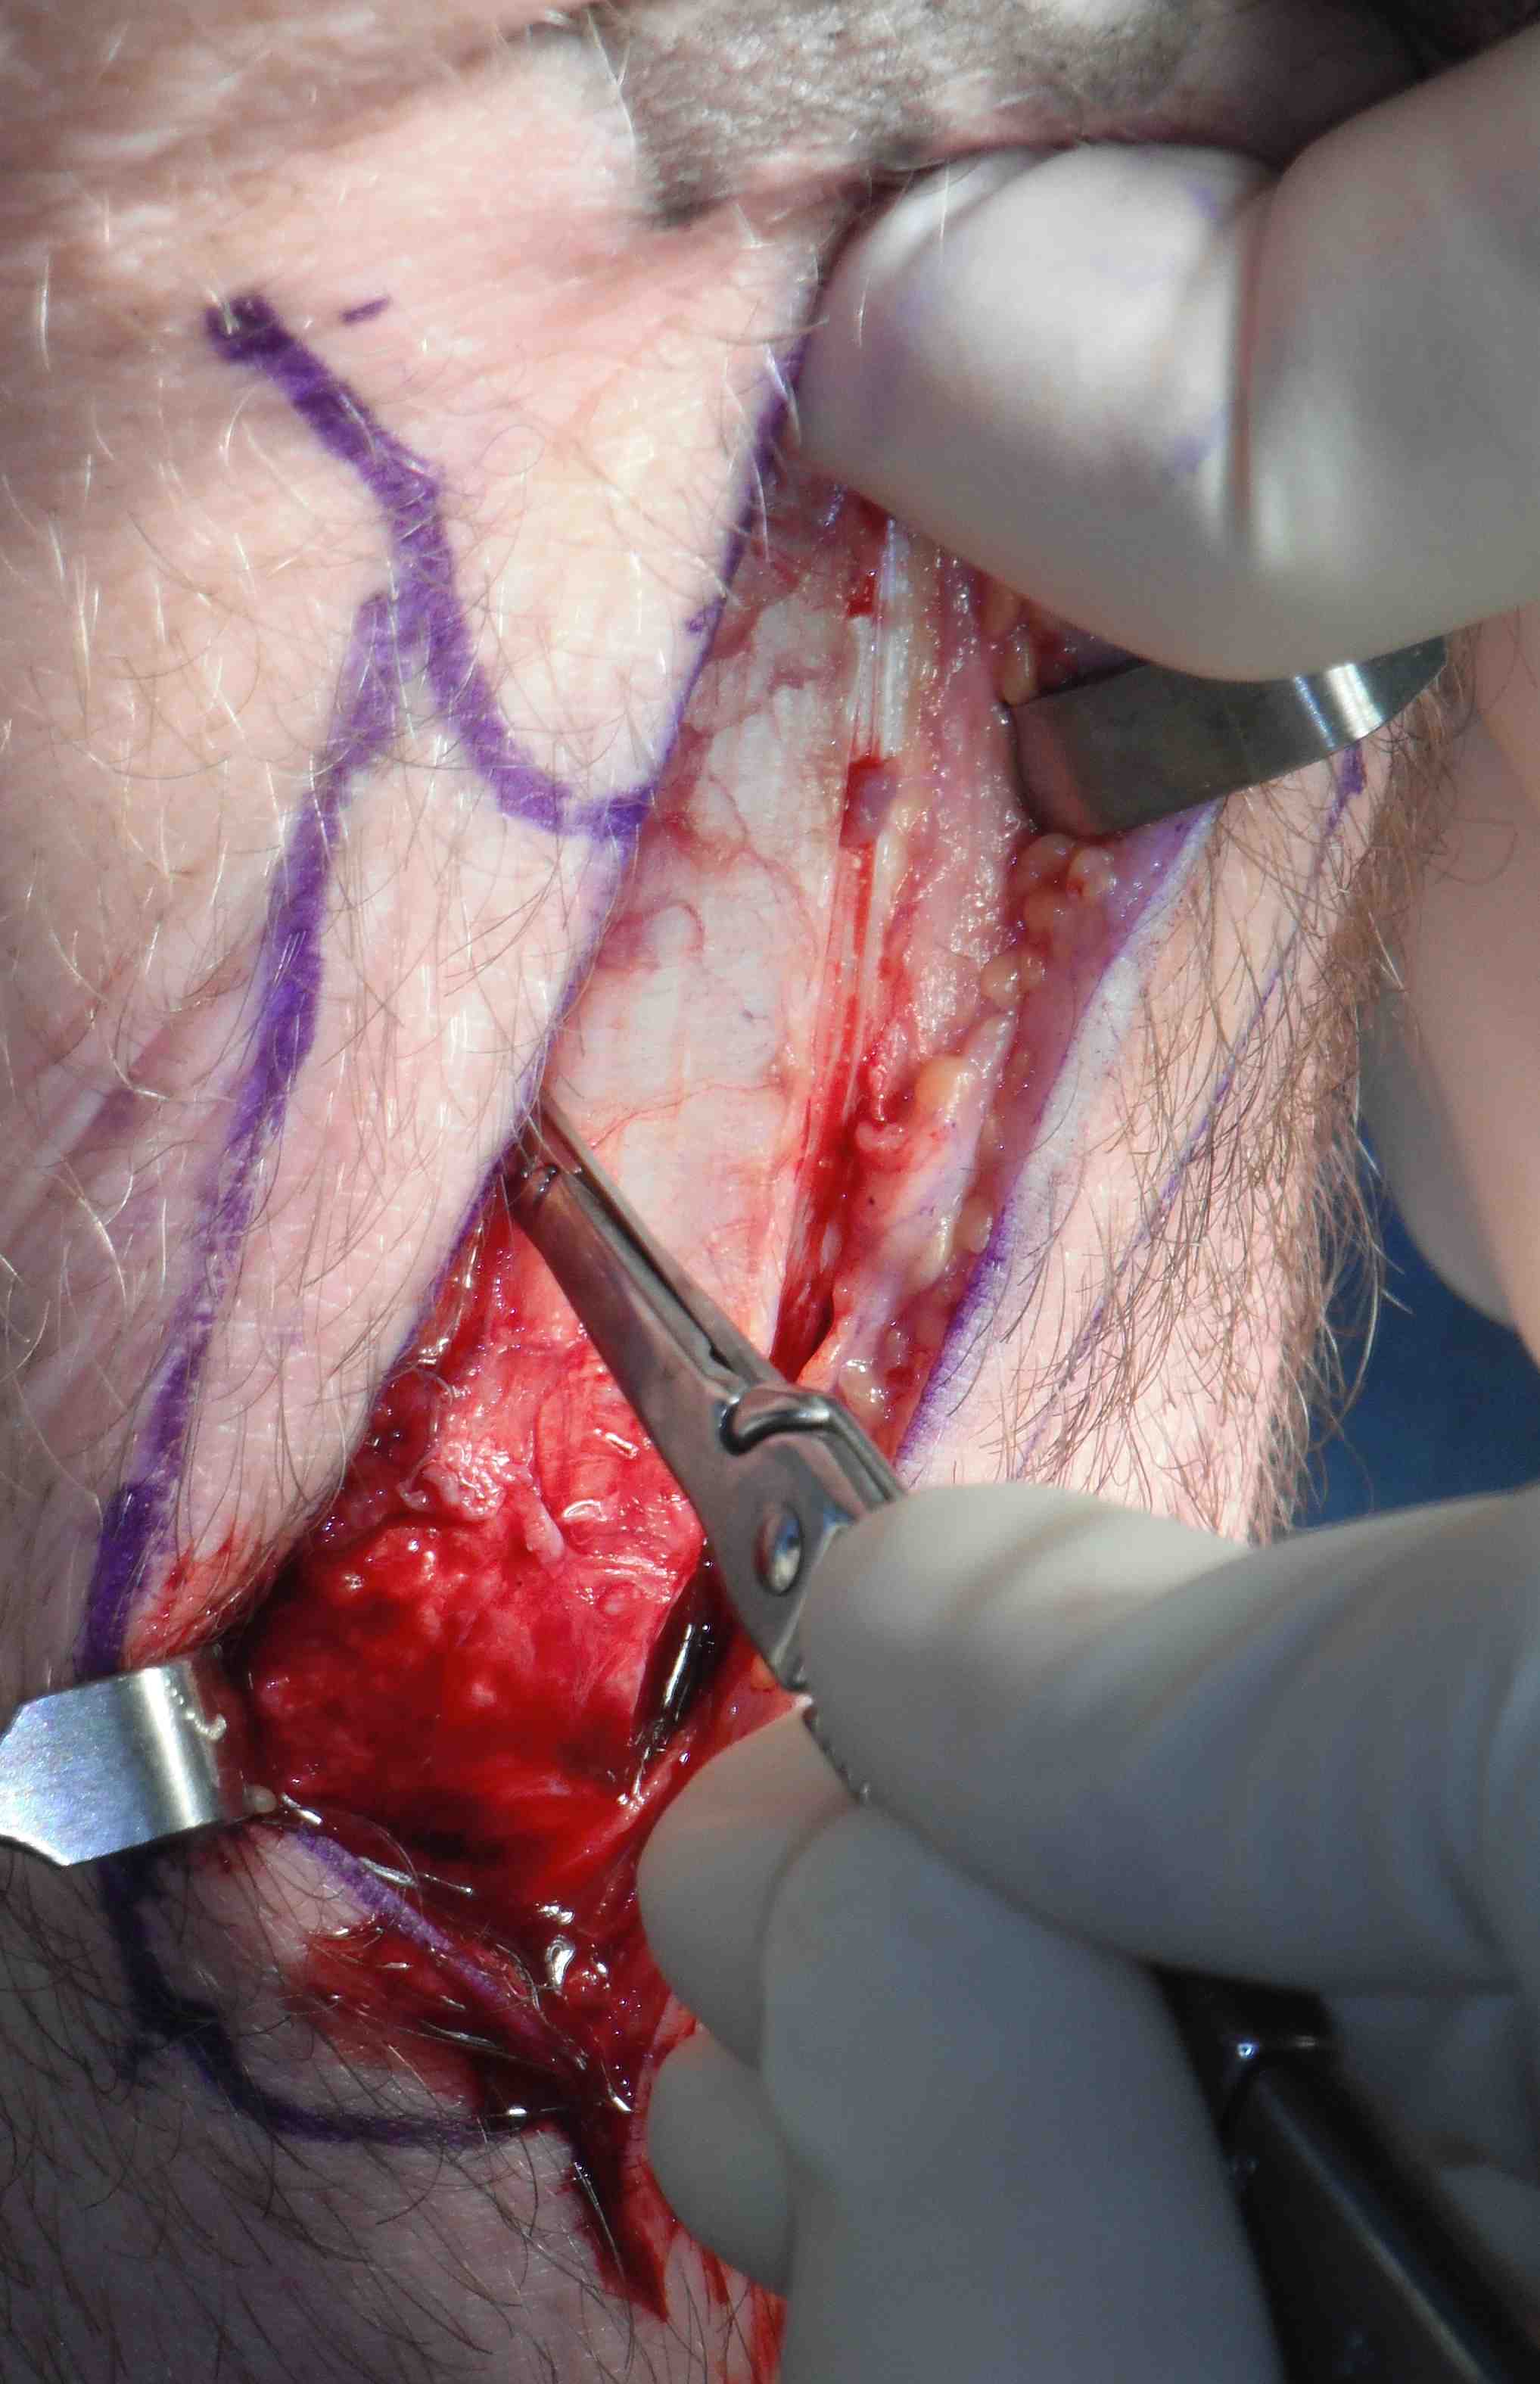

Midline incision over patella tendon

- from lower pole of patella to tibial tuberosity

- dissect fascia off tendon carefully without injuring tendon

- identify medial and lateral margins and assess tendon width

Use marking pen to mark central 1 cm of tendon at distal pole patella

- can increase this to 12 - 14 mm in large male if sufficient tendon width

- use knife to cut from 2 cm on patella down medial side

- ensure leave 5 mm tendon medially

- extend 2cm down tibial tuberosity

- remeasure and cut laterally